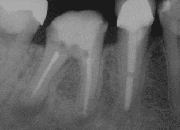

![]() تصویر اشعه X از یک دندان پس از جراحی ریشه | |